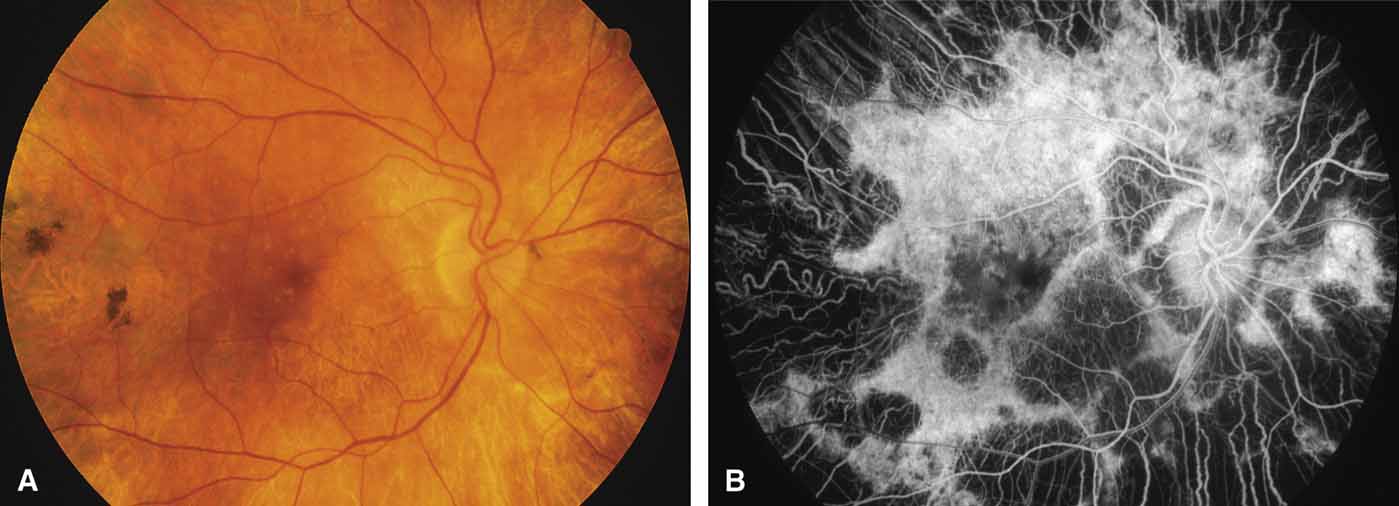

Gyrate atrophy of the choroid and retina with hyperornithinemia from ornithine aminotransferase deficiency. Gyrate atrophy of the choroid and retina (MIM No. 258870) is an autosomal recessive disease that is associated with a 10- to 20-fold elevation of plasma and tissue levels of ornithine.49–52 Vitamin B6 responsive and nonresponsive forms exist. Although the disease is found worldwide, the greatest number of patients, nearly 50% of those reported (all B6 nonresponsive), are of Finnish descent.52 In the first or second decade of life, patients experience night blindness and begin to develop irregular round areas of total vascular choroidal atrophy (Fig. 10A).50 These lesions enlarge and coalesce with time, forming extensive atrophy in the periphery that is associated with constriction of the peripheral visual field (Figs. 10B and 10C). The classic appearance of the fundus is that of a sharp transition from more normal retina to nearly complete atrophy of the choroid and retina (Figs. 11A and 11B).50,53 Central vision may be lost from cystoid macular edema, epiretinal proliferation, or macular involvement in the atrophic process (Figs. 11C and 11D).50 Many patients will develop clinically significant posterior subcapsular cataracts. The ERG and EOG are markedly abnormal from early in the course of the disease.54